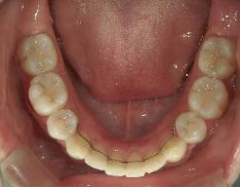

矯正歯科 治療前